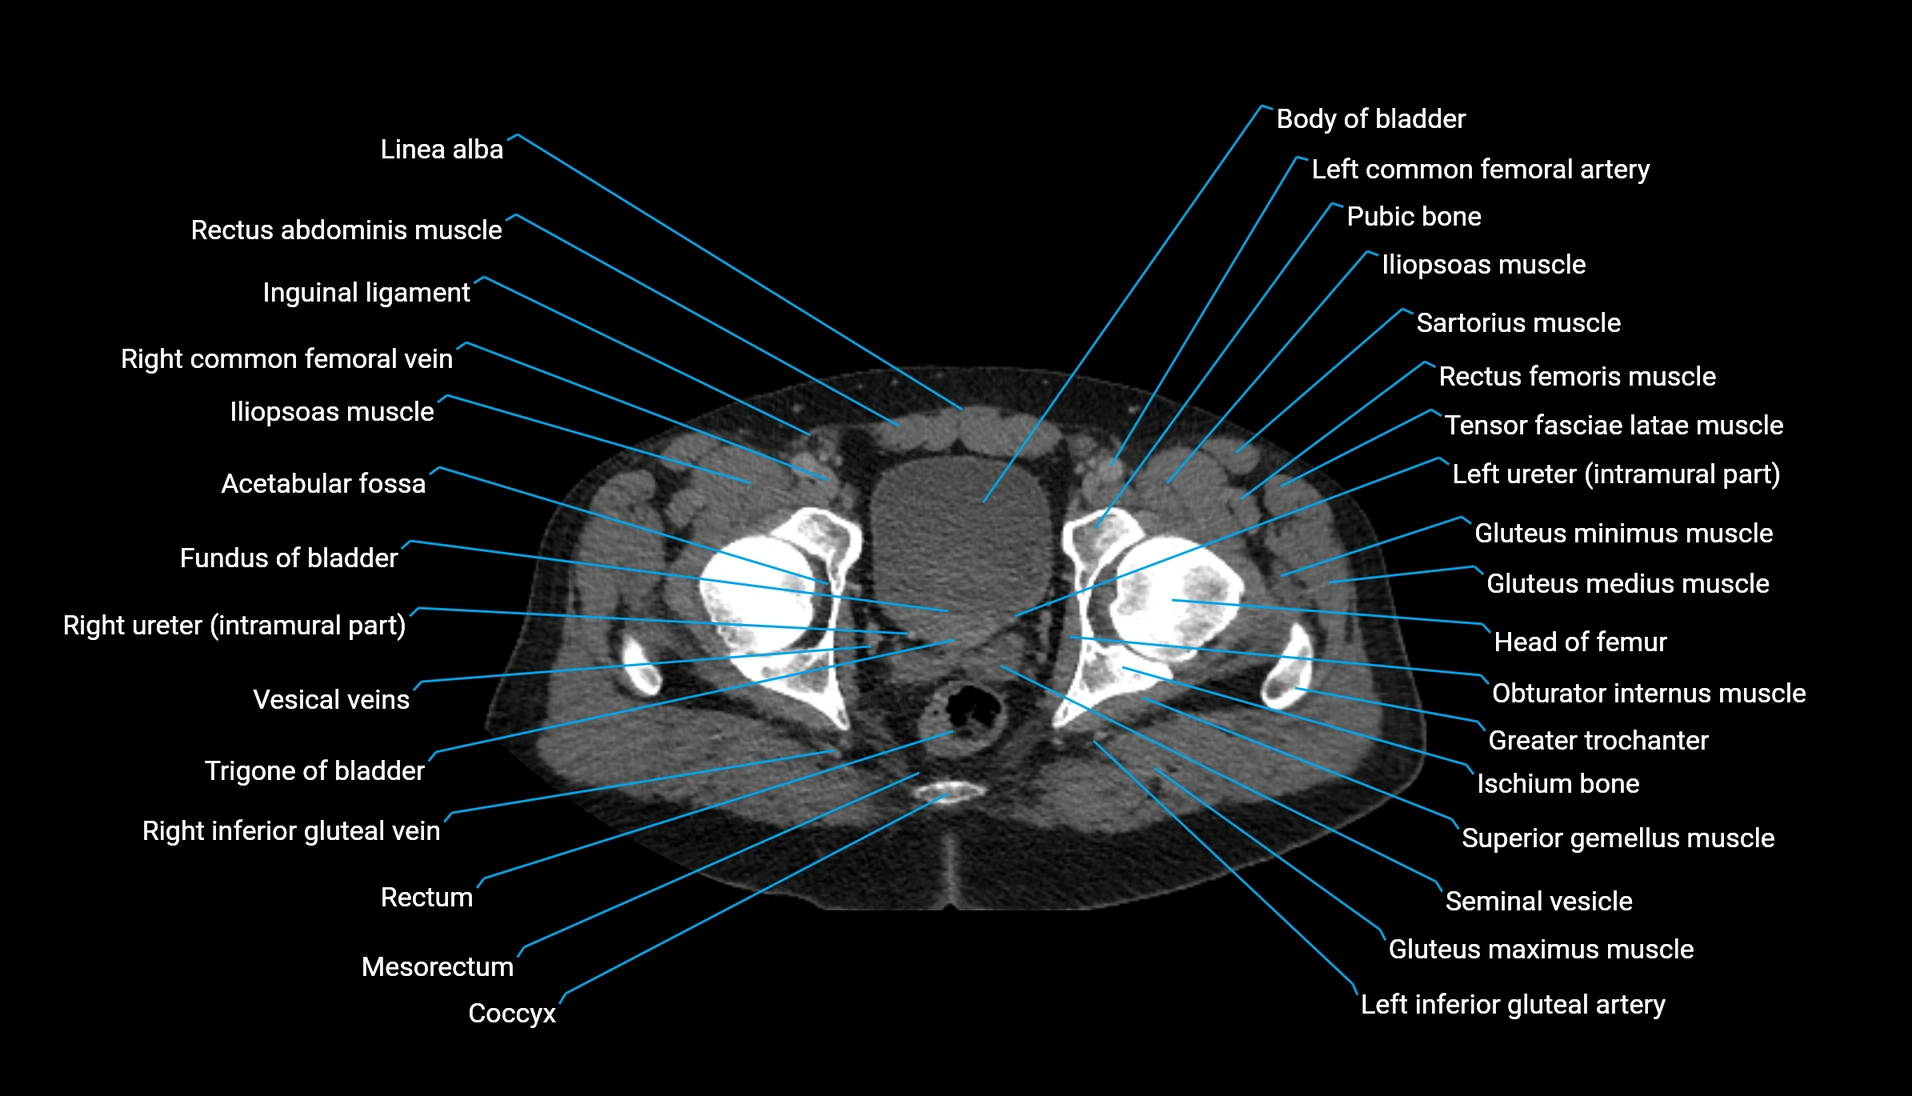

CT Appearance

Non-contrast CT:

-

Demonstrates cortical bone of acetabular rim in excellent detail

Detects fractures, dysplasia, retroversion, or bony overcoverage (pincer impingement)

3D reconstructions used in preoperative hip surgery planning

CT VRT 3D image

CT image